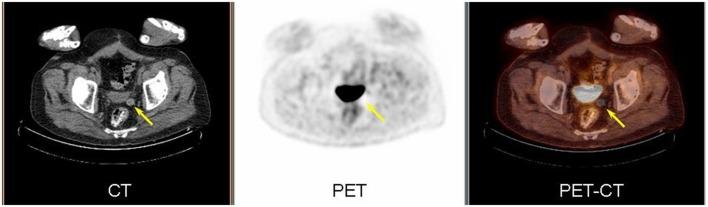

We present the case of a 77-year-old male with a history of prostate cancer. Follow up PET-CT and contrast-enhanced CT demonstrated a small peritoneal loose body or "mouse" in the pelvis. This is an uncommon, benign, asymptomatic finding which is usually incidentally discovered. The significance of being aware of this entity is to distinguish it from metastasis, especially in patients with known abdominal and pelvic malignancies.

我们报告了一例 77 岁男性前列腺癌病史。随访 PET-CT 和增强 CT 显示骨盆内有一个小的腹膜游离体或“鼠标”。这是一种不常见的良性、无症状的发现,通常是偶然发现的。认识到这种实体的意义在于将其与转移区分开来,特别是在已知有腹部和盆腔恶性肿瘤的患者中。